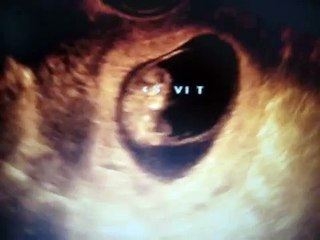

Ecografía Semana 22 (I)

Primera parte da ecografía de la 22 semana